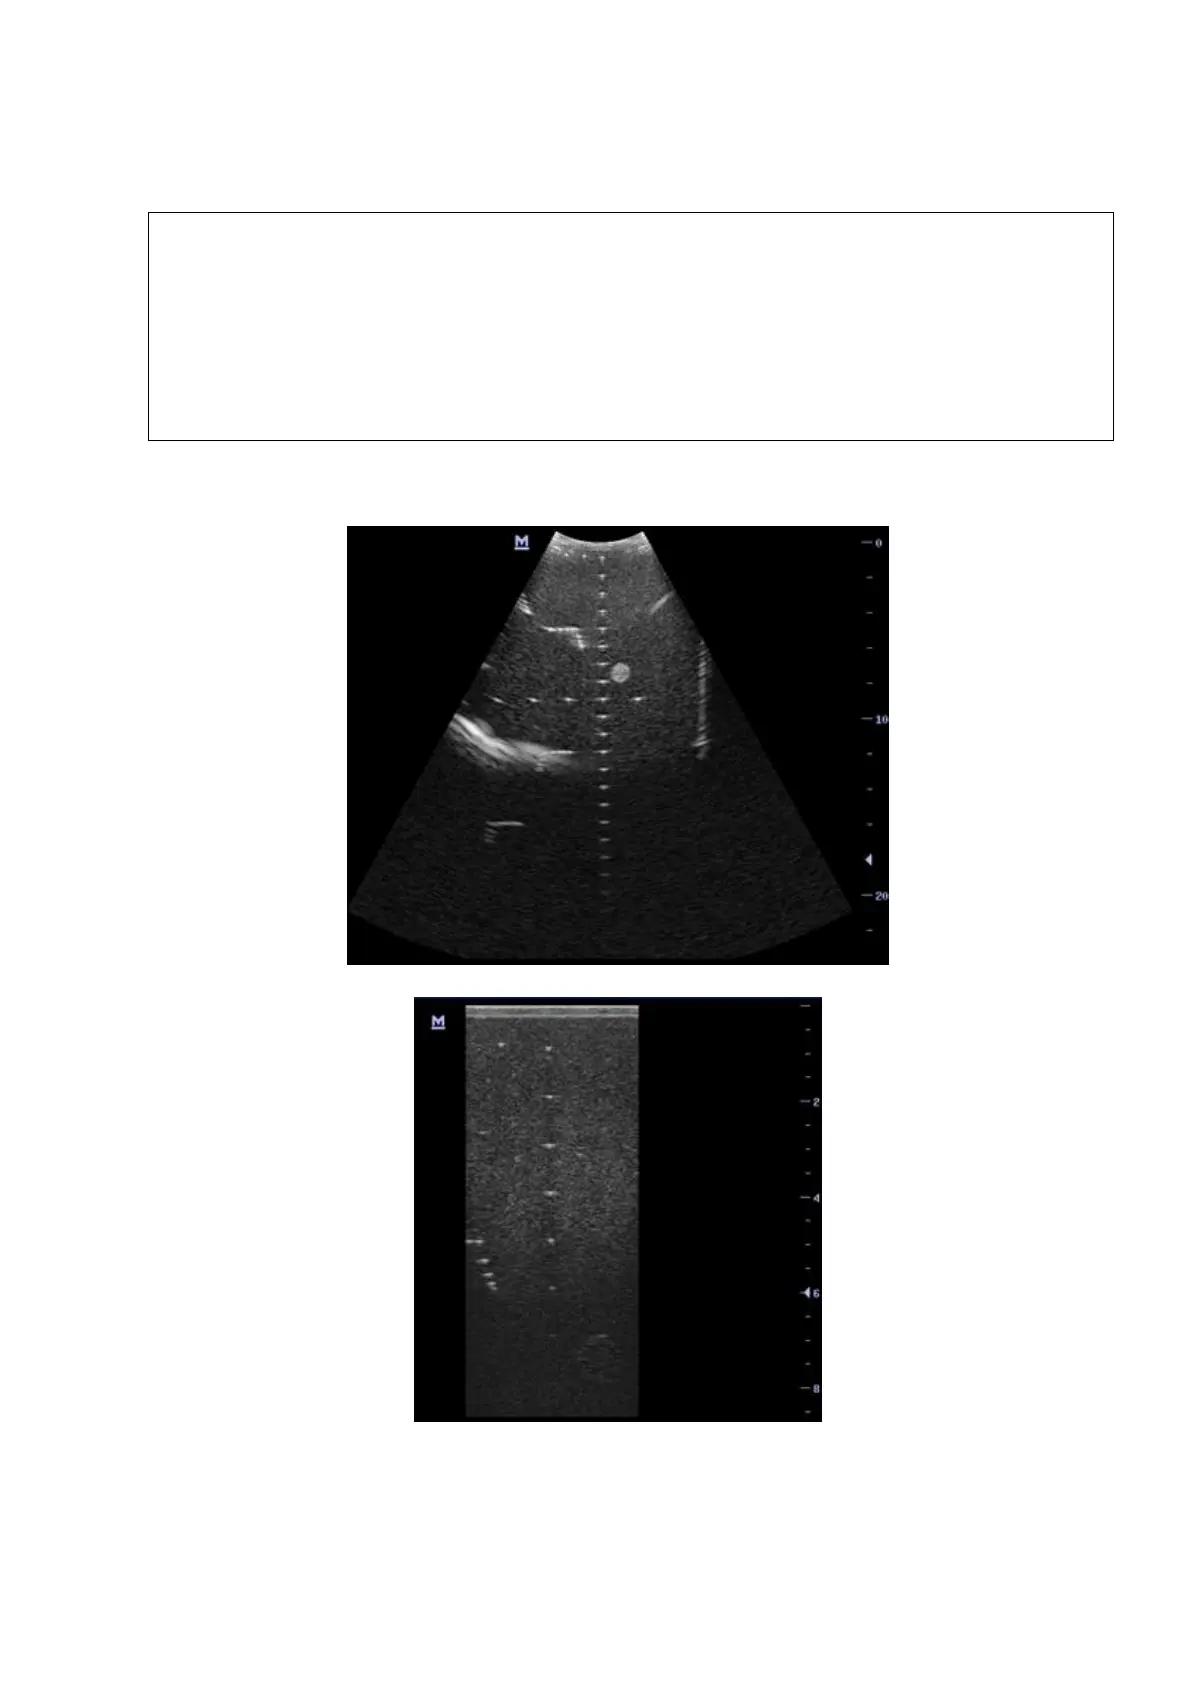

5-14 Function and Performance Checking Method

5. Record the depth of the furthest target (the target can be seen clearly).

NOTE:

1.

Increasing the gain will also increase the noise, and echo may be covered.

2.

When using a linear probe, please completely contact the probe with the scan

surface, no side clearance is allowed.

3.

When using a convex or phased-array probe, make the axis targets to be

displayed at the middle of the scanning image.

4.

When system is not frozen, the fast field target information may be similar to that

of the noise, do not use this target.

As shown in figure below.